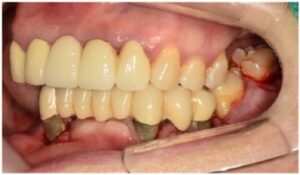

최종 보철물은

자연치아와 강도가 유사하고

심미적인 지르코니아 보철물로

마무리해 드렸습니다.

모든 치료가 마무리된

파노라마 사진과

구강 내 사진인데요.

환자분께서는

치료 후 양측 저작이 편안해지고

심미적으로 변한 모습에

만족해하셨습니다.

전 > 후